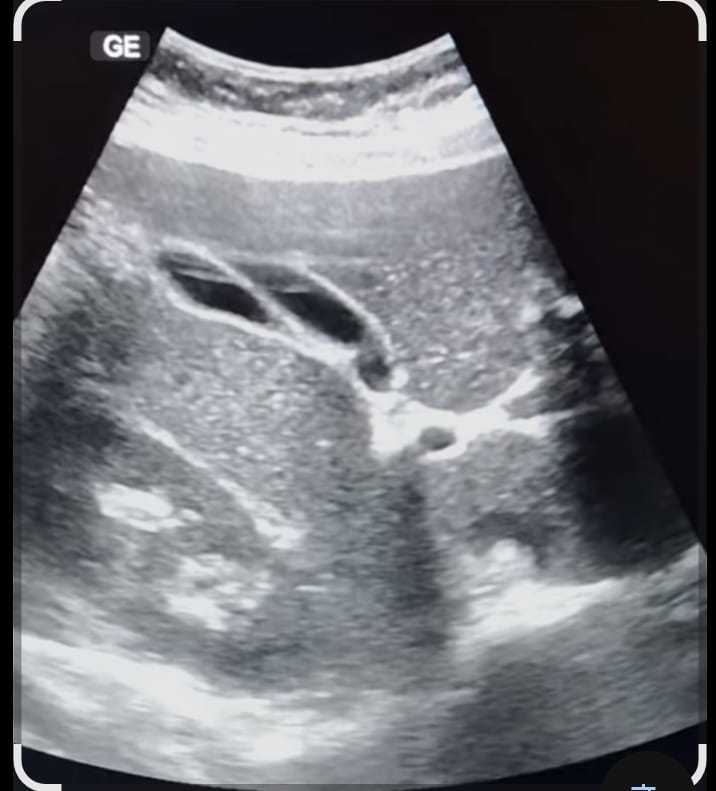

14.HEPATO BILIARY ULTRASOUND

HEPATO BILIARY ULTRASOUND-Basics of Ultrasound Imaging,Normal anatomy and pathologies of Liver,gall bladder,biliary tract,Pancreas.

15.RENAL ULTRASOUND

Basics of ultrasound imaging,Scanning techniques and protocols,Normal anatomy and pathologies of Kidney, ureters, bladder and Prostate.